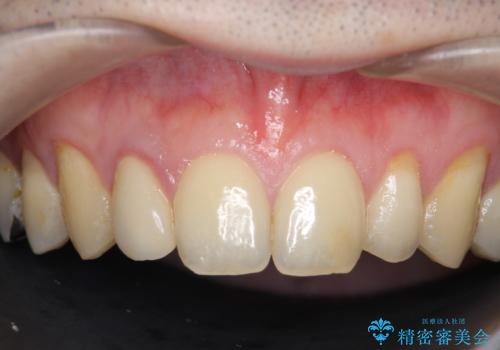

- 金属を使っていない被せ物に替えたいといらっしゃった方の症例です。

再根管治療終了後、オールセラミッククラウンによる補綴を行いました。

今回用いたオールセラミッククラウンはジルコニアフレームという白い素材の上にセラミックを盛っているため、審美性が非常に高いのが特徴です。